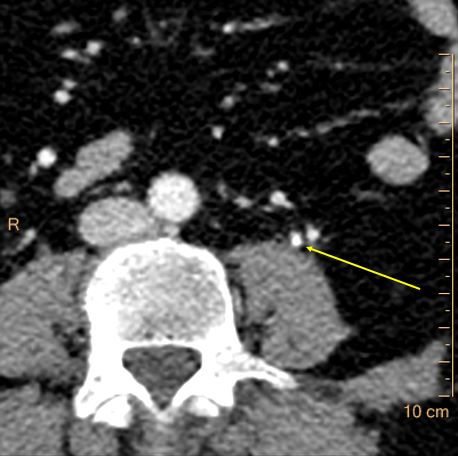

Can we tell more about the stone, than that there is a stone? Yes, of course, with Spectral CT! This calculus is made of uric acid on spectral analysis.

Stone was sent for analysis, which confirmed that it was made mostly of uric acid.

This is important, because it gives radiology a chance to go above and beyond the usual descriptions and into pathology, which is where we need to be. In this case, stone extraction was indicated because of unremitting symptoms, but in other case, a confident diagnosis of uric acid calculi may enable medical management and save the patient (and the healthcare system) procedures.

Uric acid overlay: Color coding of left ureteral stone confirms uric acid composition.